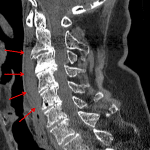

- High density prevertebral collection spanning C2-C6

- No acute fracture or traumatic malalignment

- Multilevel degenerative disease resulting in moderate to advanced central stenosis at C2-C3 through C4-C5 as well as varying degrees of multilevel neural foraminal stenosis

- Isolated prevertebral hematoma (extensive ligamentous injury found on subsequent MRI)

High density prevertebral collection spanning C2-C6 concerning for a prevertebral hematoma. While there is no CT evidence of acute fracture or traumatic malalignment, MRI of the cervical spine is recommended to exclude ligamentous injury given this finding.